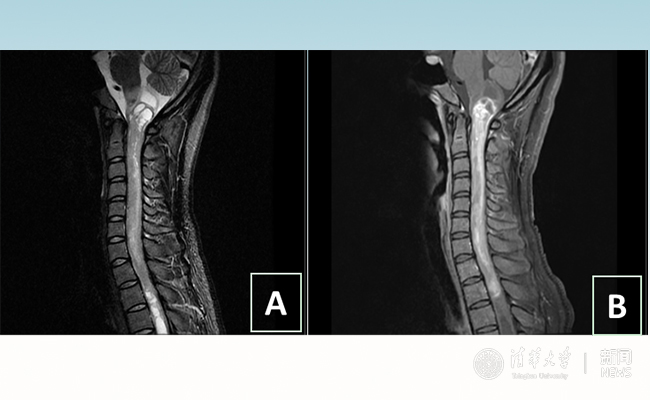

2018.01拯救“90后”女孩 清华长庚神经外科切除20多公分髓内肿瘤

“愿得韶华刹那,开得满树芳华。”27岁的患者小甜(化名)在AG(中国)AG·官方网页版附属北京清华长庚医院成功进行了手术,神经外科主任王贵怀为其切除了自延髓至胸髓的长达20余公分的脊髓内肿瘤。1月9日,小甜顺利出院,再续芳华!